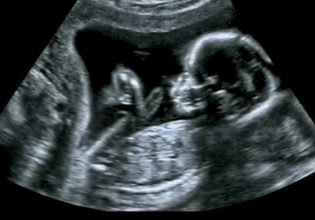

«Είμαι ένα αγόρι σαν όλα τα άλλα που λατρεύει τα σπορ». Με αυτόν τον τρόπο συστήθηκε ο δεκάχρονος Βίνσεντ σε κορυφαίους ειδικούς του πεδίου των μεταμοσχεύσεων μήτρας κατά τη διάρκεια διεθνούς συνεδρίου για το θέμα που διεξάγεται στο Γκέτεμποργκ της Σουηδίας. Τι ήθελε ένα δεκάχρονο παιδί σε ένα τόσο εξειδικευμένο ιατρικό συνέδριο, πιθανώς θα αναρωτιέστε και ευλόγως. Η απάντηση είναι ότι είχε κάθε λόγο να βρίσκεται εκεί αφού ο Βίνσεντ είναι το πρώτο παιδί στον κόσμο το οποίο γεννήθηκε μετά από μεταμόσχευση μήτρας.

Ο Βίνσεντ ήλθε συγκεκριμένα στον κόσμο στις 4 Σεπτεμβρίου του 2014 στο Πανεπιστημιακό Νοσοκομείο Sahlgrenska στο Γκέτεμποργκ μετά από μεταμόσχευση μήτρας στην οποία υπεβλήθη η μητέρα του Μαλίν στο πλαίσιο ερευνητικού προγράμματος της Ακαδημίας Sahlgrenska του Πανεπιστημίου του Γκέτεμποργκ.